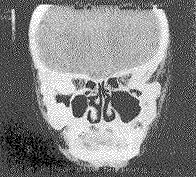

部位可见2 cm×0.5 cm的间隙,无牙齿。触诊双侧髁状突区无任何动度。X线片及CT片显示:下颌骨体部发育细小,两侧升支短粗,无髁状突,局部呈骨性融合改变,颞颌关节窝发育不良,仅见

图3 CT检查冠状位示下颌骨升支粗短与颅底融合